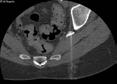

A) Coronal T2 IDEAL, B) axial diffusion tensor imaging (DTI), and C) coronal DTI fiber tracking sequences of the lumbosacral plexus and sciatic nerves demonstrates increased caliber and signal of the right sciatic nerve as it traverses the sciatic notch underneath the piriformis muscle.

D) Prone CT scan of the pelvis at the sciatic notch demonstrates a spinal needle placed at the sciatic nerve with injection of contrast and anesthetic: steroid mixture filling the perineural spaces of the sciatic nerve during a sciatic nerve block.